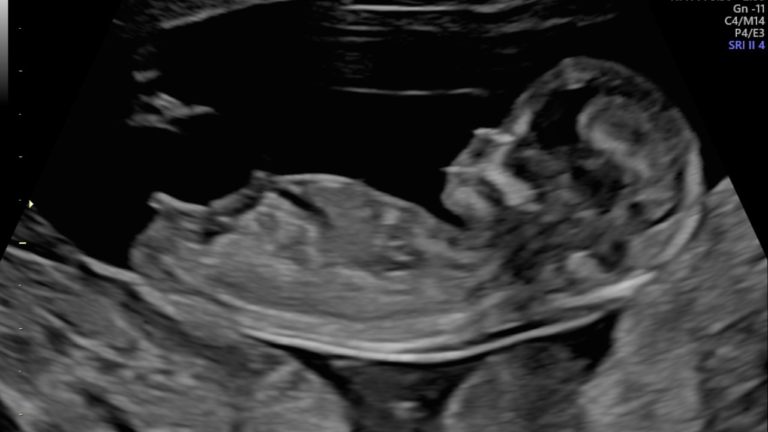

Morfológico de Primeiro Trimestre – o exame mais importante da gestação

O exame morfológico de primeiro trimestre é o exame mais importante da gravidez pois é nessa fase o melhor momento para a avaliação precoce da anatomia fetal, além de o único momento da gestação em que é possível avaliar, com boa acurácia e sensibilidade, sinais que nos indiquem se há alguma alteração genética cromossômica nesse…